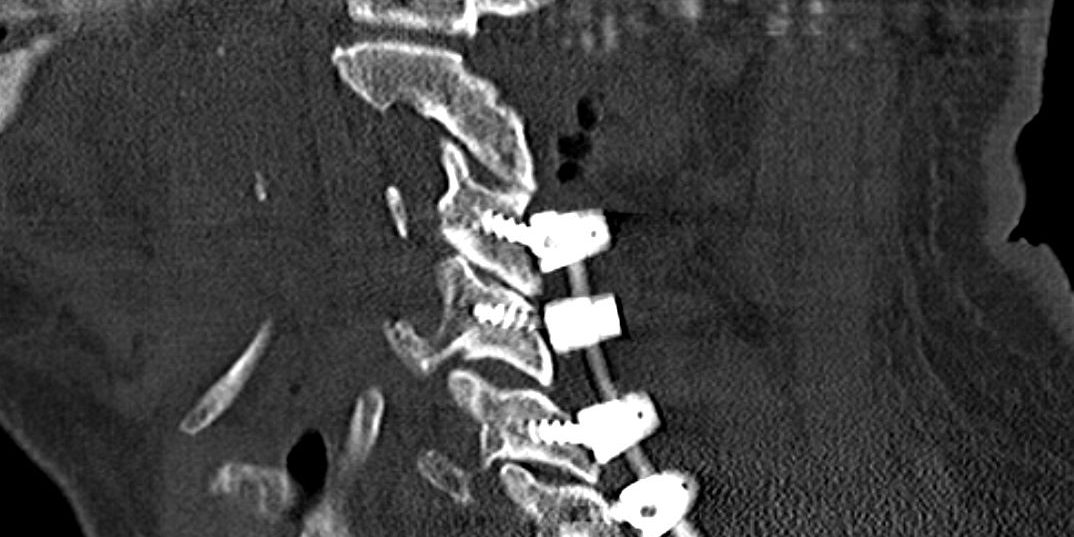

Διενεργήθη πεταλεκτομία και σπονδυλοδεσία Α3 έως Α7 σπονδύλου.

Εδώ επιλέξαμε την οπίσθια αποσυμπίεση για πολλούς λόγους: Πρώτον, υπάρχει σε πολλαπλά επίπεδα υπερτροφία των ωχρών συνδέσμων η οποία ασκεί πίεση στην οπίσθια επιφάνεια του νωτιαίου μυελού. Δεύτερον, υπάρχει σημαντική επασβέστωση του οπ. επιμήκους συνδέσμου, που σημαίνει ότι η πρόσθιες δισκεκτομές ίσως να μην καταφέρουν την πλήρη απελευθέρωση του νωτιαίου μυελού. Τρίτον, η λόρδωση της αυχενικής μοίρας είναι ικανοποιητική, γεγονός που μας επιτρέπει να αποσυμπιέσουμε με πεταλεκτομία. Παρόλα αυτά, λόγω των έντονων οστεοαρθριτικών αλλοιώσεων, επιλέξαμε επιπλέον να σταθεροποιήσουμε την αυχενική μοίρα του ασθενούς έτσι ώστε να αποφύγουμε τον πόνο από «αστάθεια» της σπονδυλικής στήλης και μια ενδεχόμενη μελλοντική παραμόρφωση της αυχενικής μοίρας.

Εδώ η αποσυμπίεση και η σπονδυλοδεσία έγιναν σε ένα χρόνο, δηλαδή στο ίδιο χειρουργείο. Μια εναλλακτική θα ήταν η αποσυμπίεση μόνο, χωρίς σπονδυλοδεσία και ενδεχόμενη σπονδυλοδεσία σε 2ο χρόνο, αν προέκυπτε ανάγκη. Και η επιλεγχθείσα στρατηγική αλλά και η εναλλακτική που μόλις προανέφερα έχουν πλεονεκτήματα και μειονεκτήματα. Η επιλογή της καταλληλότερης στρατηγικής/μεθόδου επιλέγεται -όπως εδώ- μετά από συζήτηση με τον ασθενή.